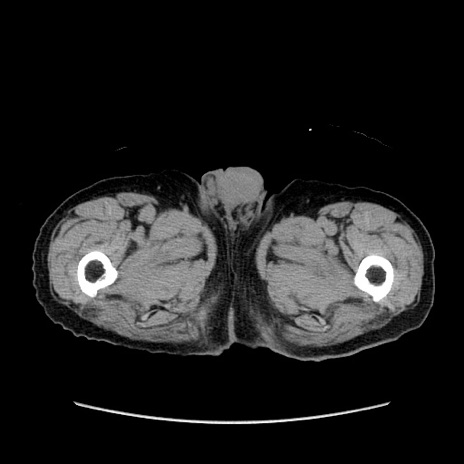

症例24(横断像)

【症例】80歳代男性

【主訴】左側腹部痛、嘔吐

【現病歴】本日早朝より左腹部に痛みあり。昼頃嘔吐認めたため、救急要請。

【既往歴】直腸癌(Mile手術)、胆摘

【身体所見】意識清明、BT 35.9℃、BP 221/93mmHg、SpO2 97%(RA) 、腹部:左ストーマ周囲に限局性の腹部膨隆あり。 膨隆部自発痛・圧痛あり・軟。

【データ】WBC 7700、CRP 0.09